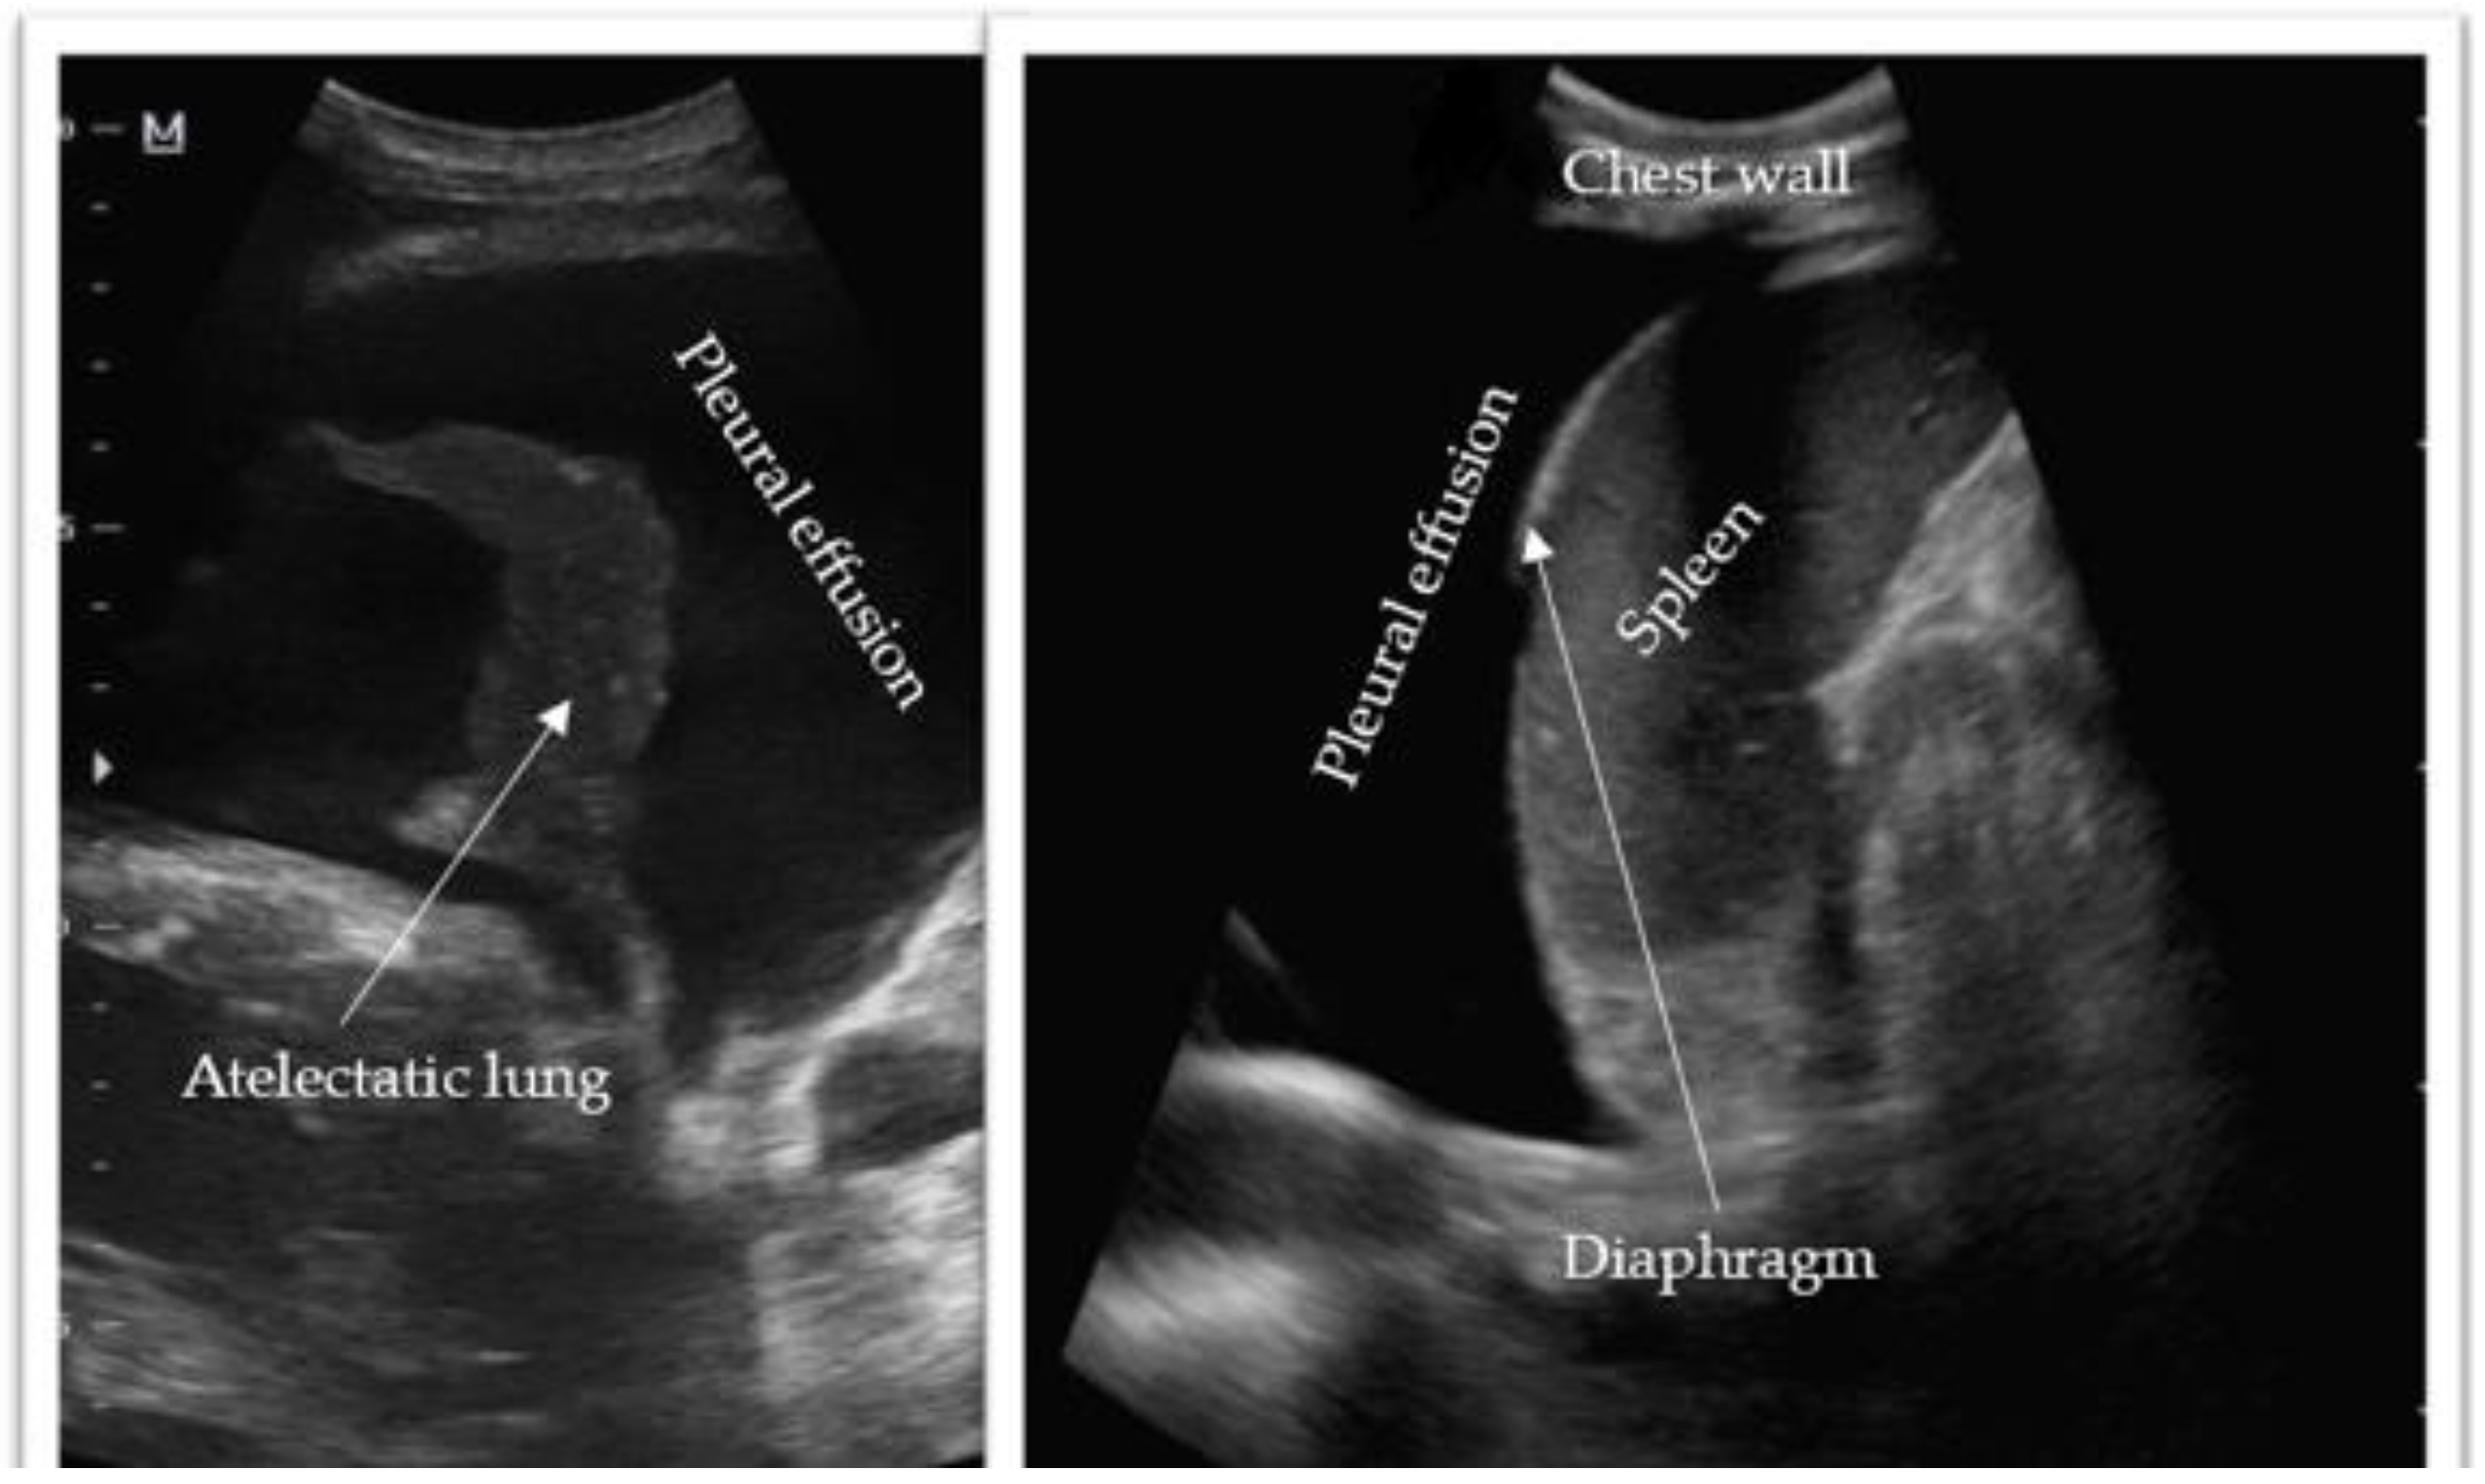

2.3.3. Ultrasound